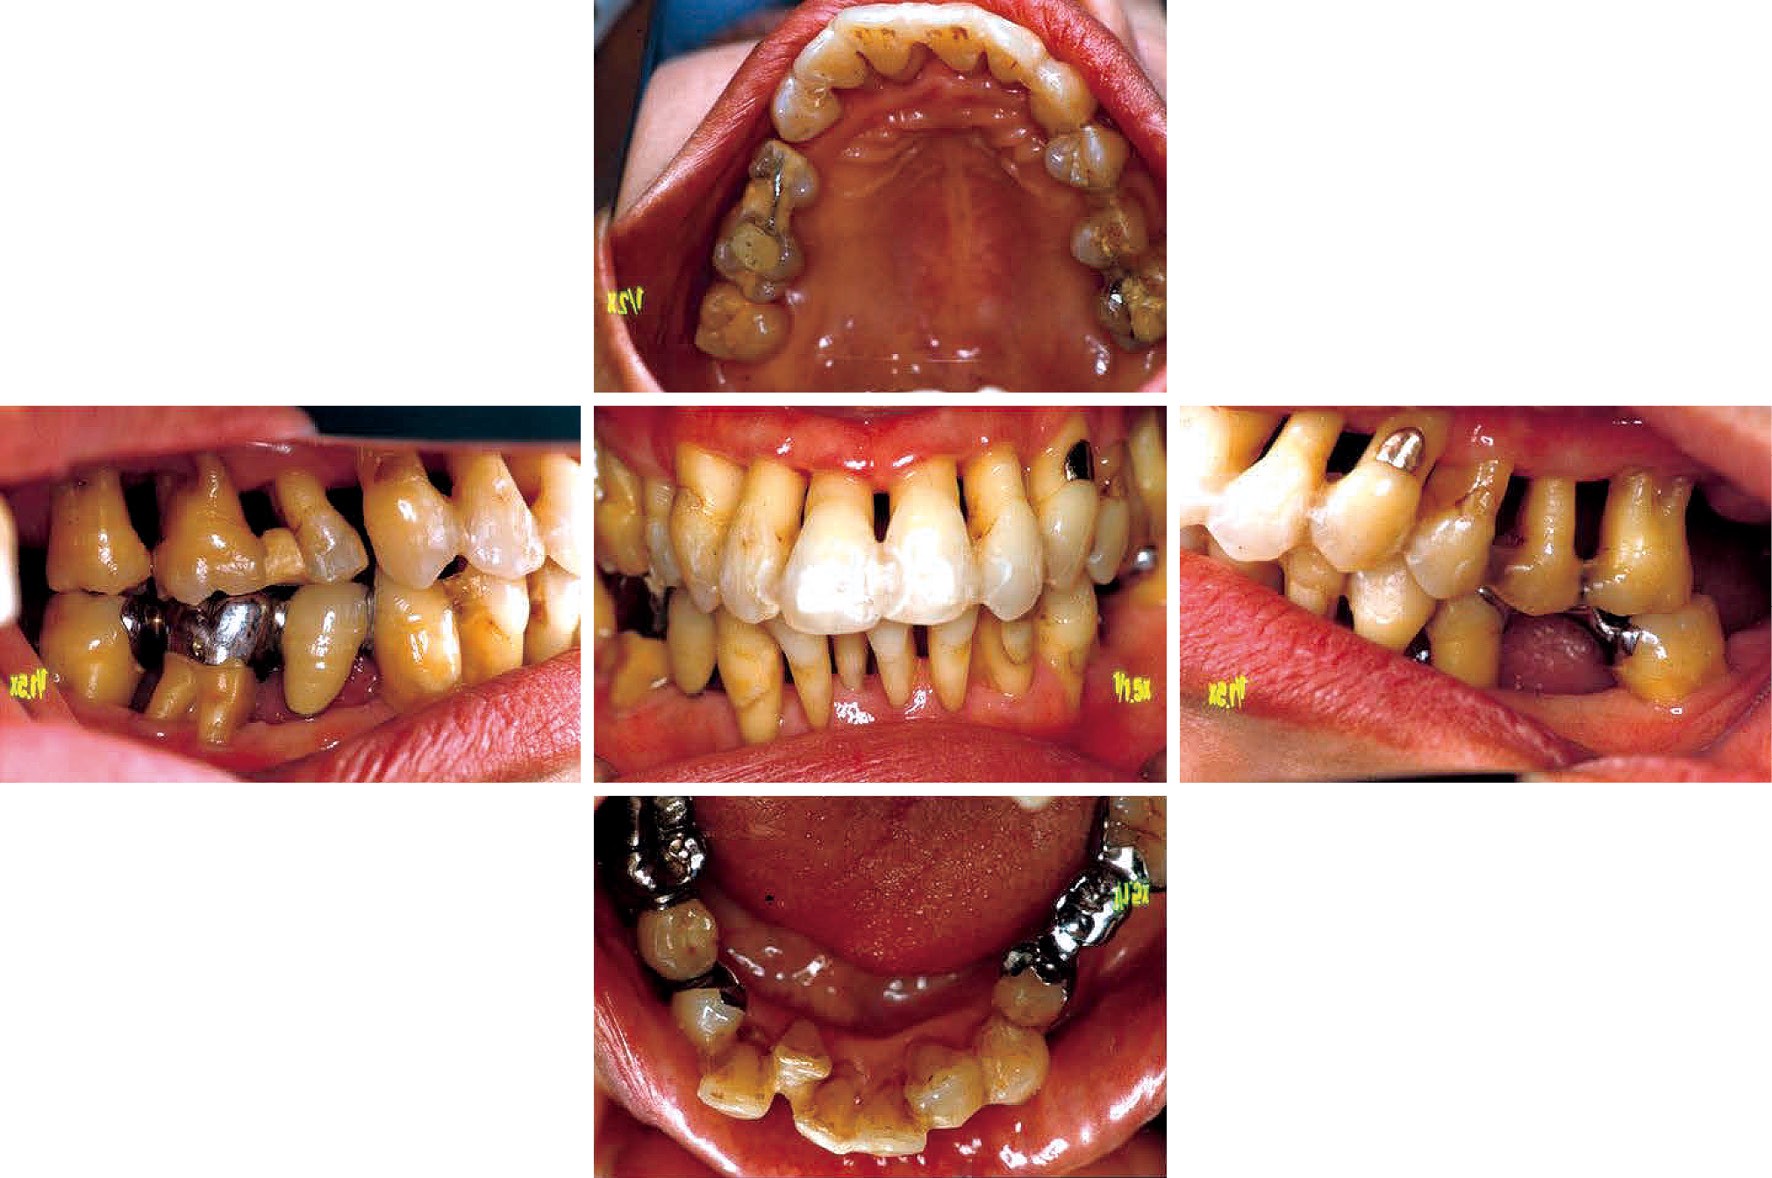

b) 治療方針と治療計画広汎型重度慢性歯周炎で喫煙関連性歯周炎でもある(図2,図3)。市場でご主人と天ぷらを揚げて販売している。仕事が多忙で,毎日疲労感が強く,睡眠も十分に取れない。重大な悩み事を持っている(内容不明)。細身体で,明らかにタバコ臭がある。歯周組織検査後,病状の説明を行い,治療計画を説明した。その際,希望があれば「禁煙指導」をする旨伝えたが,受諾はなかった。当時(平成6年)は現在ほど禁煙キャンペーンに熱心ではなかったことも災いしている。しかし,歯肉退縮,年齢42歳でかなりやせ型,タバコ臭と喫煙の悪影響がみられ,深いポケット残存部へのフラップ手術も計画しづらく,また再発の危険性も高いため,プラークコントロールレベルの改善に加えて禁煙達成を歯周外科手術実施の条件として計画を立てた。患者から得られた情報は歯周組織所見(図2)として歯根露出(歯肉退縮),歯の挺出,歯の着色,歯石沈着等であった。歯肉に発赤・腫脹の炎症所見が認められる。同様に,エックス線写真(図3)より,全顎的に高度な歯槽骨吸収がみられ,37および47は既に欠損し,17,16,12,11,22,24,25,26,27,31,41,42はほぼ根尖に至る骨吸収像,上下大臼歯はすべて根分岐部病変に罹患していることが分かった。

初診時(42歳,女性)の口腔内写真。

c) 治療経過とSPT重度の広汎型慢性歯周炎患者の初診時の病態写真(図7)とエックス線写真(図8)で,病態写真は一部紛失している。近隣歯科医の下でプラークコントロールや縁上スケーリング処置は受けたものの,外科処置やリコールの設定がなされなかったものである。高度な歯周組織破壊と著しい歯肉退縮が特徴である。ただ,動揺の揺れ幅や安定性に関しては頬舌方向の揺れより近遠心方向の揺れが明らかに少ない。14,35,44,45に歯の欠損があるものの,歯列の連続性が保たれていて,咬合圧等の外力に連座して抵抗できていたものと考える。そこで,二次性咬合性外傷への対策およびブラッシング時の機能的動揺への不安軽減を考慮して,計画の最重要点として,①隣接面を共有する全歯への暫間固定(前歯B-スプリント,臼歯A-スプリント),②欠損部への暫間義歯の装着の2つを掲げて処置を継続した。プラークコントロールは常時良好で,PCR値は10%前後に落ち着いていた。

初診時の口腔内写真(51歳,女性)(左:正面観,右:上顎口蓋側面観(鏡像反転))